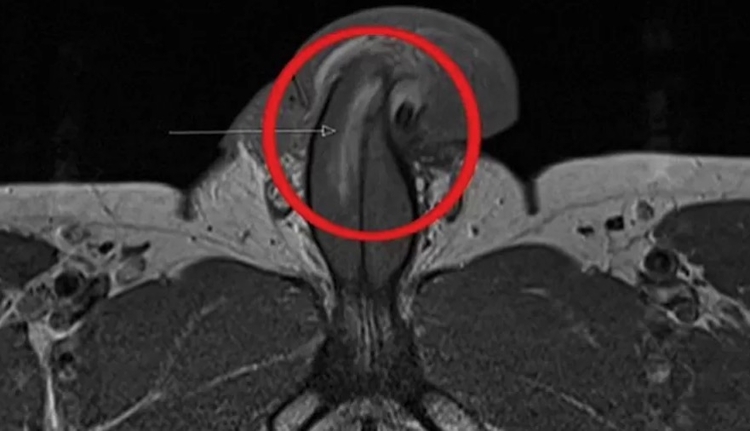

Segundo a publicação, a lesão foi constatada em uma ressonância magnética e não há nenhum caso registrado igual documentado até hoje.

De acordo com o relatório, o ferimento aconteceu quando o pênis bateu contra o períneo (espaço entre o ânus e os genitais) da parceira provocando uma dobra.